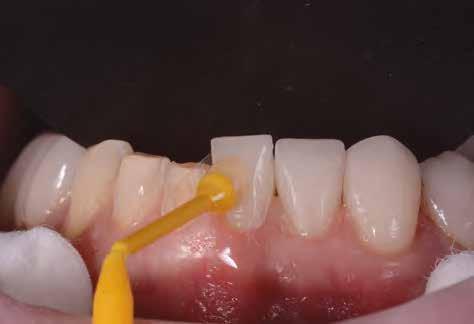

Szájterpesz használata mellett digitálisan intraorális fotók készültek a páciensről mind frontális, mind laterális és okkluzális irányokból. További fotók is készültek a páciensről egy digitális tükörreflexes kamera segítségével (frontális és laterális irányból, valamint 45 o-os szögből). Mindkét állcsontról digitális lenyomat készült egy intraorális szkenner segítségével (Care stream 3500). A maximális-interkuszpidációs helyzetet (IKP) szintén a Carestream 3500-as készülék felhasználásával rögzítet -

5. ábra: A mosolytervezéshez szükséges felvétel. A mosolygó páciensről az ajak- és a bucca eltartásával készített fotó.

8. ábra: Az őrlőfogak esetében nem volt szükség foganyag elvételre. Az alsó metszőfogak minimál invazív módon lettek előkészítve, a felső frontfogak esetében megőriztük az eredeti csiszolt csonkok formáját. 7. ábra: Két évvel később, a végleges helyreállítás megkezdése előtt készített felvétel (2017).